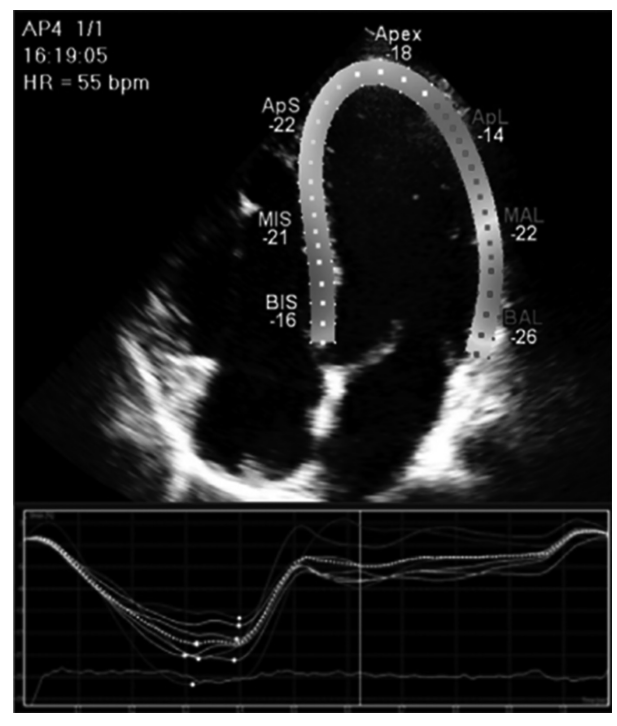

A figura a seguir representa um corte apical quatro câmaras ao ecocardiograma transtorácico mostrando o cálculo do strain global longitudinal (GLS), que descreve a mudança relativa do comprimento do miocárdio do ventrículo esquerdo entre a diástole final e sístole final por meio da fórmula GLS% = (MLs – MLd)/MLd.

Dados: ML: comprimento miocárdico, MLd: comprimento miocárdico diastólico, MLs: comprimento miocárdico sistólico.